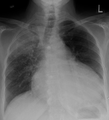

The so-called "water-bottle heart" is a radiographic sign of pericardial effusion, in which the cardiopericardial silhouette is enlarged and assumes the shape of a flask or water bottle.

A CT scan image showing a pericardial effusion

A very large hemorrhagic pericardial effusion due to malignancy as seen on ultrasound. closed arrow: the heart, open arrow: the effusion- Pericardial effusion due to malignancy. Note bulbous heart and primary lung cancer in right upper lobe.